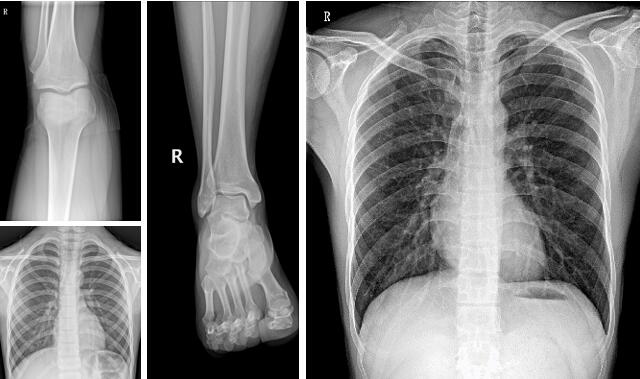

【PLX M5320移動DR臨床圖像】

3、骨科。操作方便、工作效率高,可移動dr機-PLX M5320可滿足人體的頭部、四肢、胸腔、脊柱、腰椎、腹部等全身各部位的數字化攝影的工作需求。

移動DR機PLX M5320采用大功率50kW球管可穩定輸出高品質X射線,保證優質的圖像品質,即便是腰椎側位也能得到清晰的影像,圖像質量媲美固定DR。

PLX M5320采用17×17英寸的大尺寸無線平板探測器,視野寬闊,擺位輕松。16比特灰階度,穩定輸出高分辨率、高解析度的圖像。